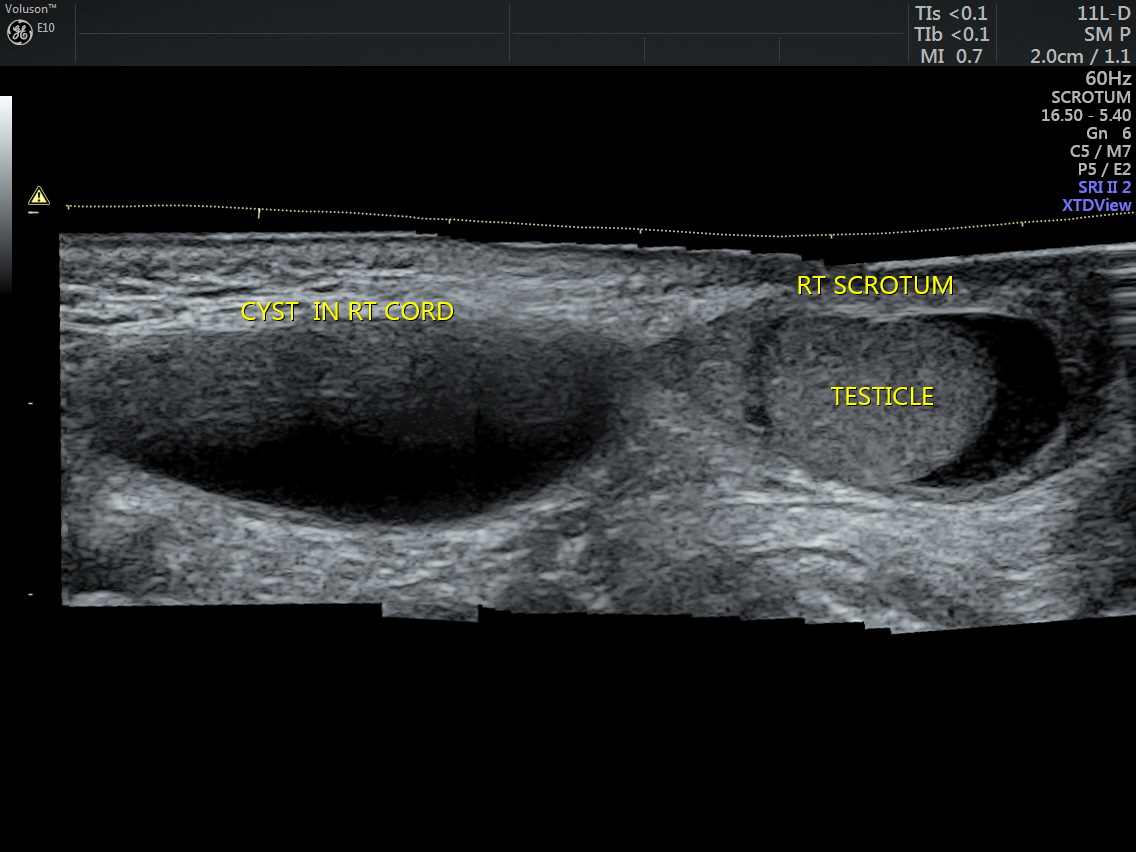

Ultrasound showed the two testicles in the scrotal sac and a cystic swelling above the right testis, distinctly separate from the same. Both the testicles appeared to have normal echotexture.

Panaoramic view of the same is given below.

This appears to be a ENCYSTED HYDROCELE OF THE SPERMATIC CORD.